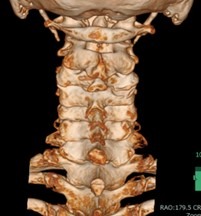

首で多い病気

• 変形性頚椎症

• 頚椎椎間板ヘルニア

• 頚椎症性脊髄症

• 頚椎後縦靭帯骨化症

首から手にかけての痛みやしびれ、手指の巧緻運動障害(細かい動作ができない)、歩行困難、膀胱直腸障害等の症状を伴う、上記のような病気があります。

• 頚椎椎弓形成術

適応となる疾患

頚椎症性脊髄症、頚椎後縦靭帯骨化症など

神経を圧迫している骨成分をチタン製のプレートを用いて挙上させることにより、狭くなった脊柱管を拡大させます。手術創もなるべく小さく当院では本手術を行っております。

術前

術後

術後創部